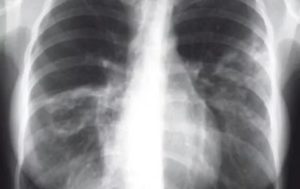

Достоверная визуальная диагностика плевральных шварт возможна только если соединительно-тканные образования больше 1 см в толщину. В противном случае тень от спаек накладывается на ткань легкого и не видна на рентгенограмме. При указании на характерные жалобы, которые возникли и сохраняются после перенесенного плеврита, требуется проведение дополнительных исследований таких, как:

Для обнаружения легочных заболеваний в первую очередь используется флюорография. Эту процедуру необходимо проводить ежегодно, в основном она направлена на выявление ранней стадии туберкулеза. Однако опытный рентгенолог может выявить на снимке образовавшиеся плевральные спайки, которые выглядят тенями. Причем форма их не меняется в зависимости от вдоха и выдоха.

При необходимости дополнительно назначается рентген. Как правило, спайки располагаются в нижней части легкого. При этом будет более темная картинка, а также может быть частичная деформация грудной клетки и диафрагмы.

На снимках тяжи выглядят затемненными участками легочного поля с усиленным сосудисто-соединительнотканным рисунком. При множественных поражениях определяются диффузные затемнения. Также возможно снижение высоты стояния ребер, уменьшение межреберного пространства и смещение органов.